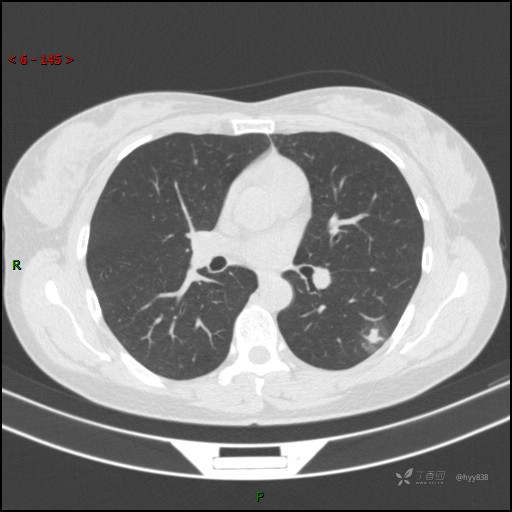

胸膜下“煎鸡蛋征”,感染 VS 炎症 VS 肿瘤,挑战有你---结果公布~

简要病史:干咳半月伴左胸部不适

辅助检查:CT

临床诊断:结节

讨论:病变性质?